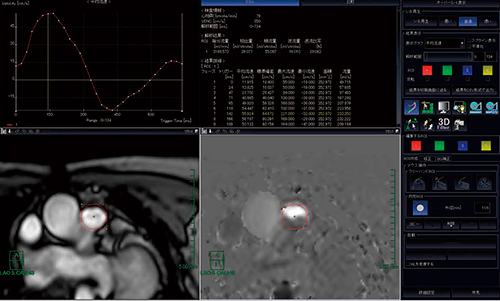

2.flow解析

PC法により,各血管・弁・人工血管のflow画像を撮像し,“MRフロー解析”ソフトウェアにて血流量や拍出量などの解析を行う。ここで,より正確なROI設定を行うことが,より良い解析結果を得ることにつながるため,撮像する際には的確なVENC(velocity encoding)値を設定し,信号強度の高い位相差画像を得ることに気を付けて検査している。

解析はROIの設定のみで瞬時に結果が表示され,逆流率やQp/Qs(肺体血流比)などの比較結果もすぐに確認することが可能である(図3)。

当院のCHD MRI検査では,大動脈,上下大静脈,主肺動脈,左右肺動脈,肺静脈,三尖弁,僧帽弁のflow解析より,正確な血流量測定や短絡血流量の測定結果が得られている。

図3 “MRフロー解析”による上行大動脈の血流量解析